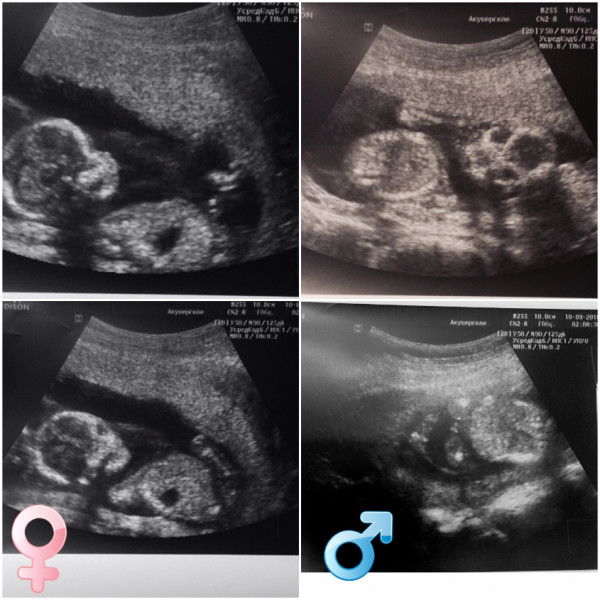

На 16 неделе малшыш весит приблизительно 80-100 г, а его рост колеблется в пределах 10-12 см. По размеру он похож на небольшое авокадо или средний помидорчик. Уже сформировалась система кроветворения и можно определить группу крови и резус. Малыш уже держит головку прямо и может вертеть ею из сторны в сторону. Начинают постепенно работать кишечник, желчный пузырь и печень. Также работают почки и мочевой пузырь, малыш начинает ходить "по-маленькому" и делает это довольно часто — примерно каждые 45 минут. Однако повода для беспокойства нет. Околоплодные воды меняются около 10 раз в сутки и абсолютно стерильны. Половые органы четко диференциированы и на узи будущим родителям уже уверенно скажут пол малыша.